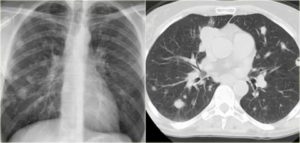

Плотность одиночных очагов в легких, определяемая при КТ, позволяет разделить все очаги на три группы:

- очаги по типу “матового стекла”;

- смешанные или частично солидные очаги;

- очаги солидного типа.

Очаги по типу “матового стекла” отличаются низкой плотностью, на их фоне видны стенки бронхов, контуры сосудов и элементы измененного легочного интерстиция. Они наблюдаются при недеструктивных воспалительных процессах, атипичной аденоматозной гиперплазии и высокодифференцированных аденокарциномах.

Морфологическая основа данного феномена заключается в утолщении межальвеолярных перегородок на ограниченном участке при сохранении воздушности альвеол, что может возникать за счет воспалительной инфильтрации, фиброзных изменений или частичного заполнения альвеол экссудатом.

При развитии аденокарциномы (в том числе и бронхиолоальвеолярной) опухолевые клетки располагаются вдоль стенок альвеол, длительное время не заполняя их просвет.

В результате возникает опухолевый очаг по типу “матового стекла”, который в большинстве случаев не виден на рентгенограммах и линейных томограммах.

Очаги смешанного или частично солидного типа характеризуются наличием более плотного участка в центре и зоны низкой плотности по типу “матового стекла” по периферии. Такие очаги обычно возникают вокруг старых рубцов в легочной ткани, в том числе и посттуберкулезных.

В большинстве случаев они представляют собой разрастание железистой опухоли.